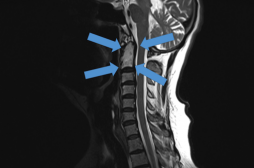

J ai Mal Bras et mains Bras et mains Tête et cou Torse et haut du dos Jambes et pied